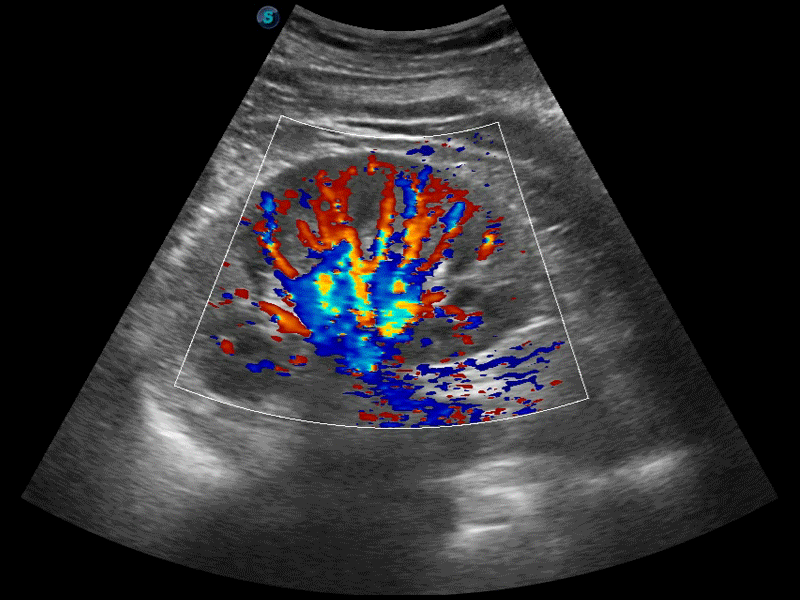

• SR Flow高分辨率血流成像技术

高分辨率血流成像技术提高了对低速血流信号的检测能力。在提高空间分辨率的同时,也克服了血流外溢现象,为用户提供更加真实的血流动力学信息。